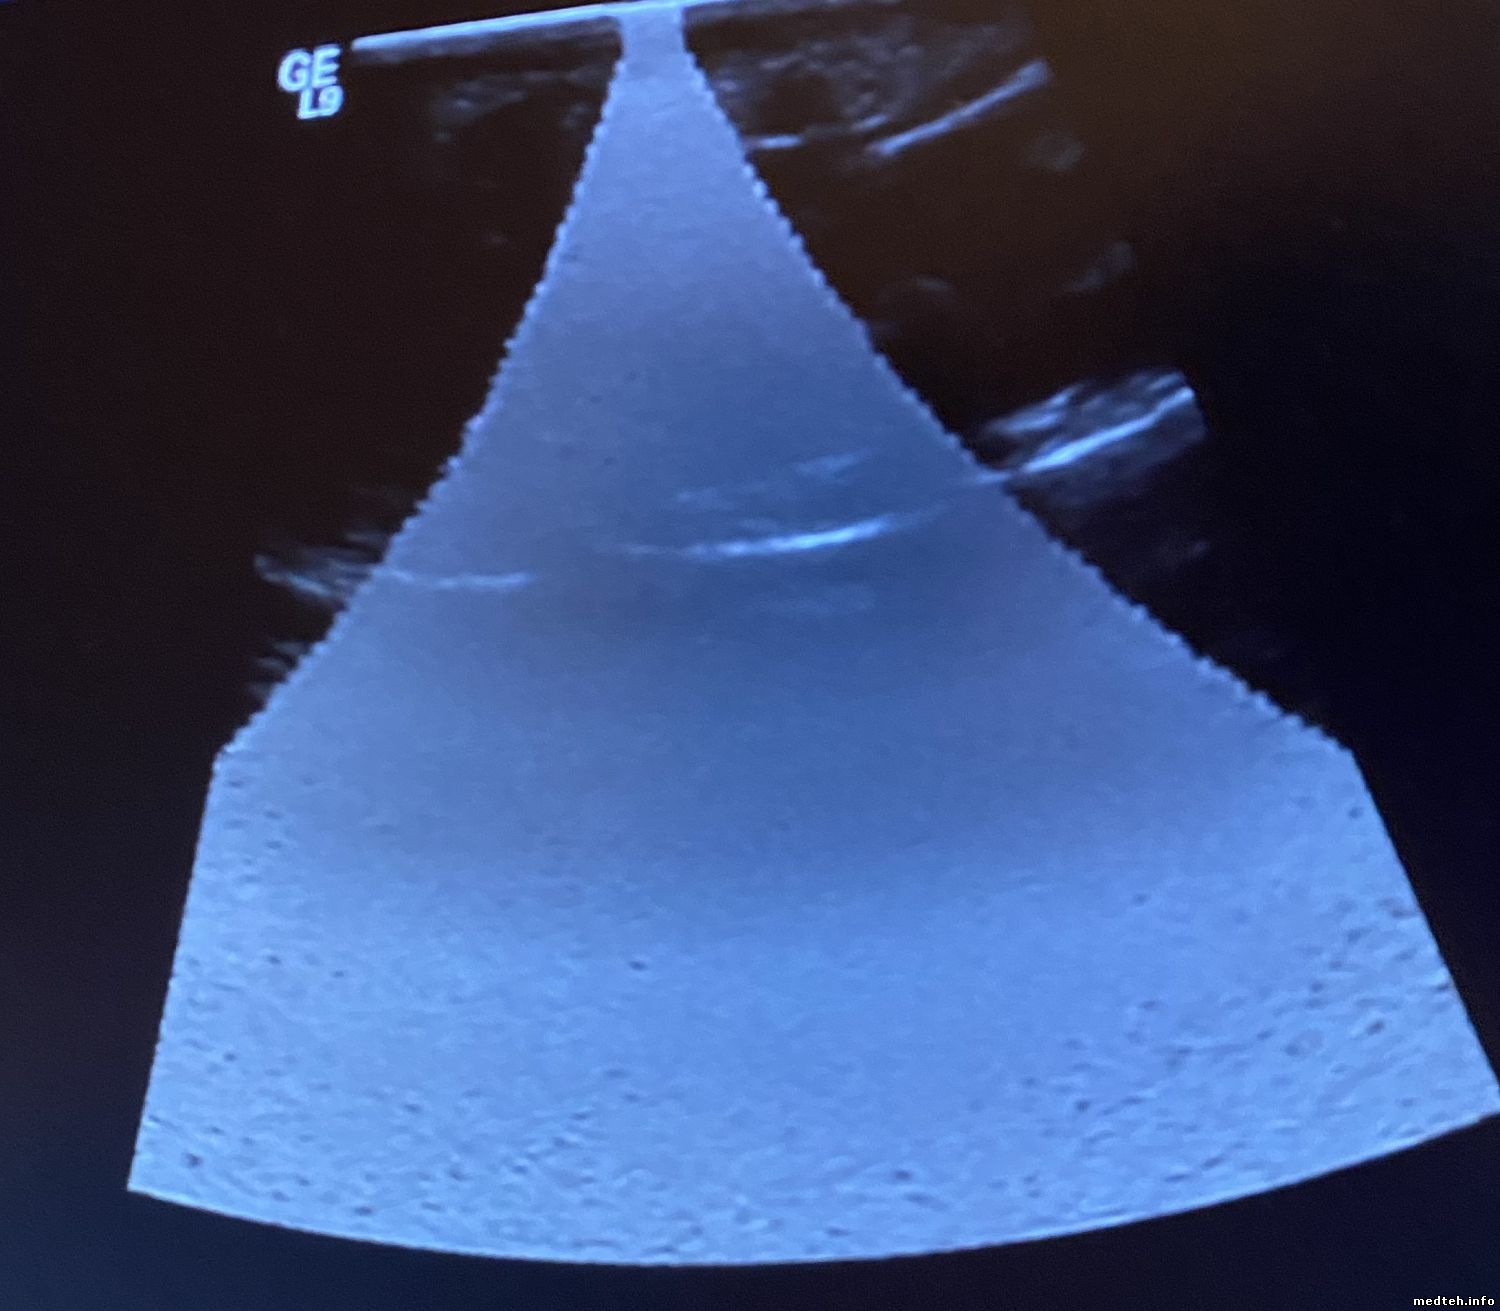

У меня по изображении Logiq 9 BT 3 появился атрефакт - на картинках. виден разной формы на всех датчиках...

боковой - круг на вагинальном, центральный конус на линейке, на конвексе ...

На конвексе:

2858277.jpg (262.1 Kb)